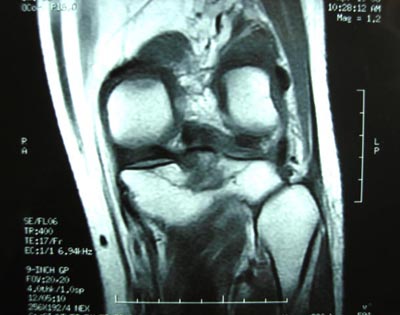

男,45。骑摩托车摔伤左膝肿痛三天,浮髌(+),活动受限。请大家看看片子有问题吗?

标题: 现将mri结果公布

手术证实是后交叉韧带胫骨附着处撕脱骨折。

术中用可吸收螺钉固定。